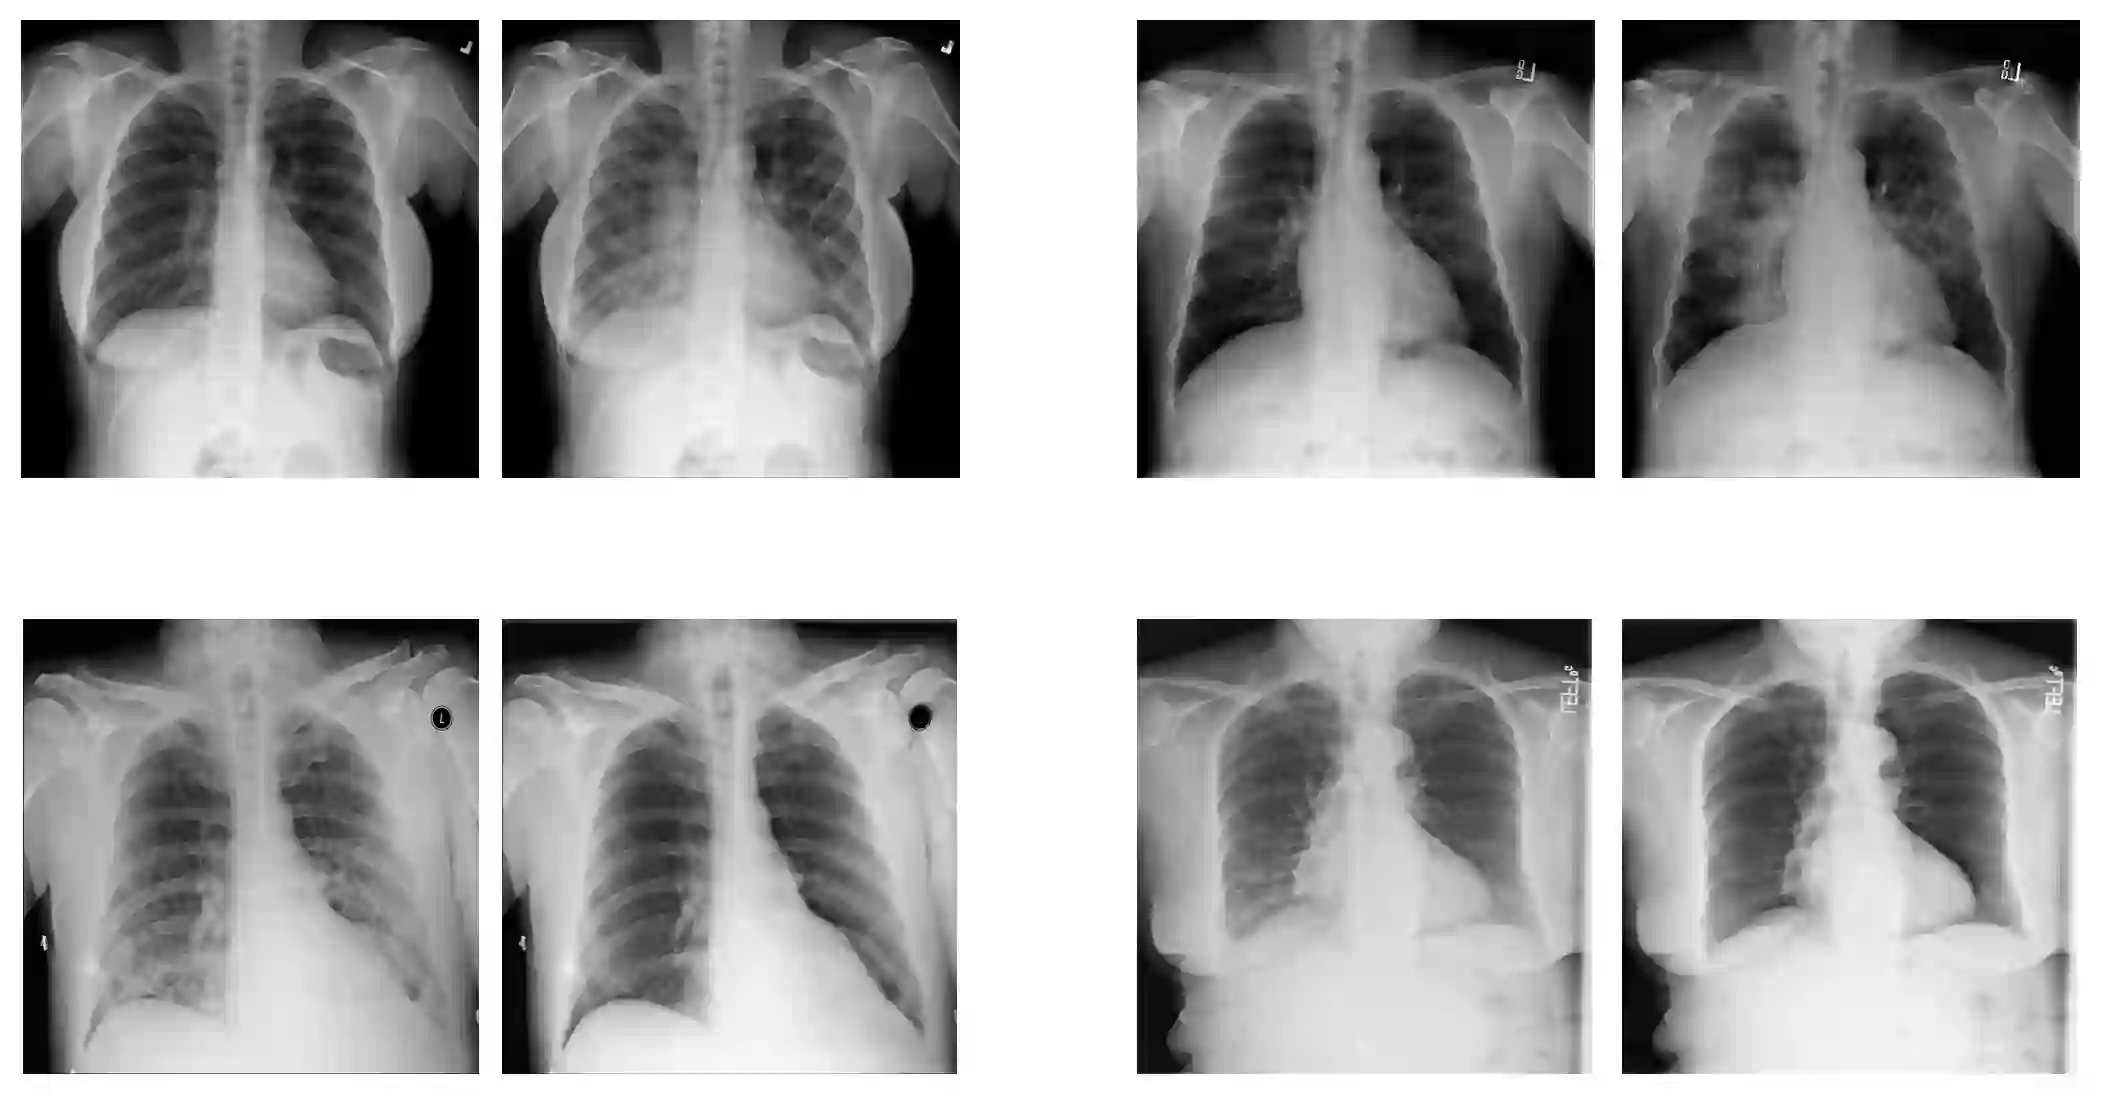

With the ongoing rise of machine learning, the need for methods for explaining decisions made by artificial intelligence systems is becoming a more and more important topic. Especially for image classification tasks, many state-of-the-art tools to explain such classifiers rely on visual highlighting of important areas of the input data. Contrary, counterfactual explanation systems try to enable a counterfactual reasoning by modifying the input image in a way such that the classifier would have made a different prediction. By doing so, the users of counterfactual explanation systems are equipped with a completely different kind of explanatory information. However, methods for generating realistic counterfactual explanations for image classifiers are still rare. Especially in medical contexts, where relevant information often consists of textural and structural information, high-quality counterfactual images have the potential to give meaningful insights into decision processes. In this work, we present GANterfactual, an approach to generate such counterfactual image explanations based on adversarial image-to-image translation techniques. Additionally, we conduct a user study to evaluate our approach in an exemplary medical use case. Our results show that, in the chosen medical use-case, counterfactual explanations lead to significantly better results regarding mental models, explanation satisfaction, trust, emotions, and self-efficacy than two state-of-the-art systems that work with saliency maps, namely LIME and LRP.

翻译:随着机器学习的不断兴起,对人工智能系统所作决定的解释方法的需要正在成为一个越来越重要的主题。特别是对于图像分类任务而言,许多最先进的解释这类分类工具依赖输入数据的重要领域的视觉突出显示。相反,反事实解释系统试图通过修改输入图像来促成反事实推理,使分类者能够作出不同的预测。通过这样做,反事实解释系统的用户配备了完全不同的解释性信息。然而,为图像分类者提供现实的反事实解释的方法仍然很少。特别是在医学方面,相关信息往往由文字和结构信息组成,高质量的反事实图像有可能为决策过程提供有意义的洞察力。在这项工作中,我们介绍了GANterfactal, 一种根据对抗图像到图像翻译技术产生这种反事实图像解释的方法。此外,我们进行了用户研究,以在典型的医疗使用案例中评价我们的方法。我们的结果显示,在所选择的医学案例中,反事实解释性解释方法往往包括文字和结构信息,高质量的反事实图像图像图像图像能够给决策过程带来更深刻的满意度,也就是两张的自我解释,而令人信得更满意。